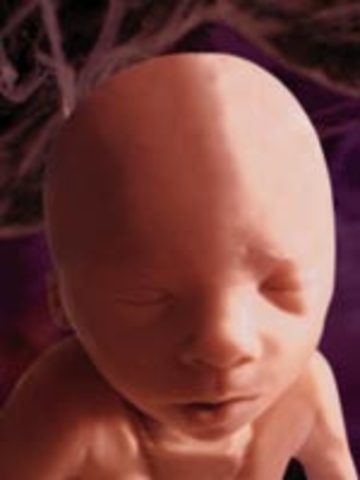

The babay's vocal chords have fully developed. In addition, the baby's brain is fully formed and is able to recognize pain, the kidneys have also formed.

• Week Thirteen Developments

Week Thirteen Developments

In this stage the fetus is around 25 grams and about 8 cm long. The baby cartilage is beginning to be replaced by bone, and the chin and nosed are becoming well defined.